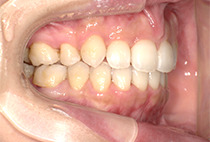

出っ歯と前歯のガタつきにお悩みだった20代女性の症例です。

金属アレルギーがあるため、メタルフリーで治療できる【インビザライン】による抜歯矯正を選択されました。

矯正治療2年6ヶ月

インビザライン、インプラントアンカー、美容治療

また、気になっていたオトガイ(顎先)の左右差に対して、

を行い、フェイスラインも自然に整えました。